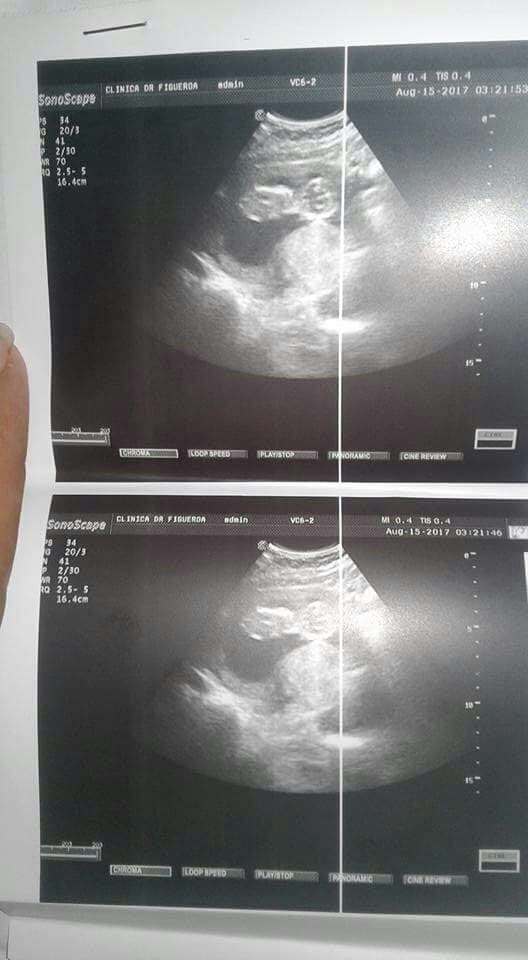

Duda sobre ecografia

yo veo un bebe